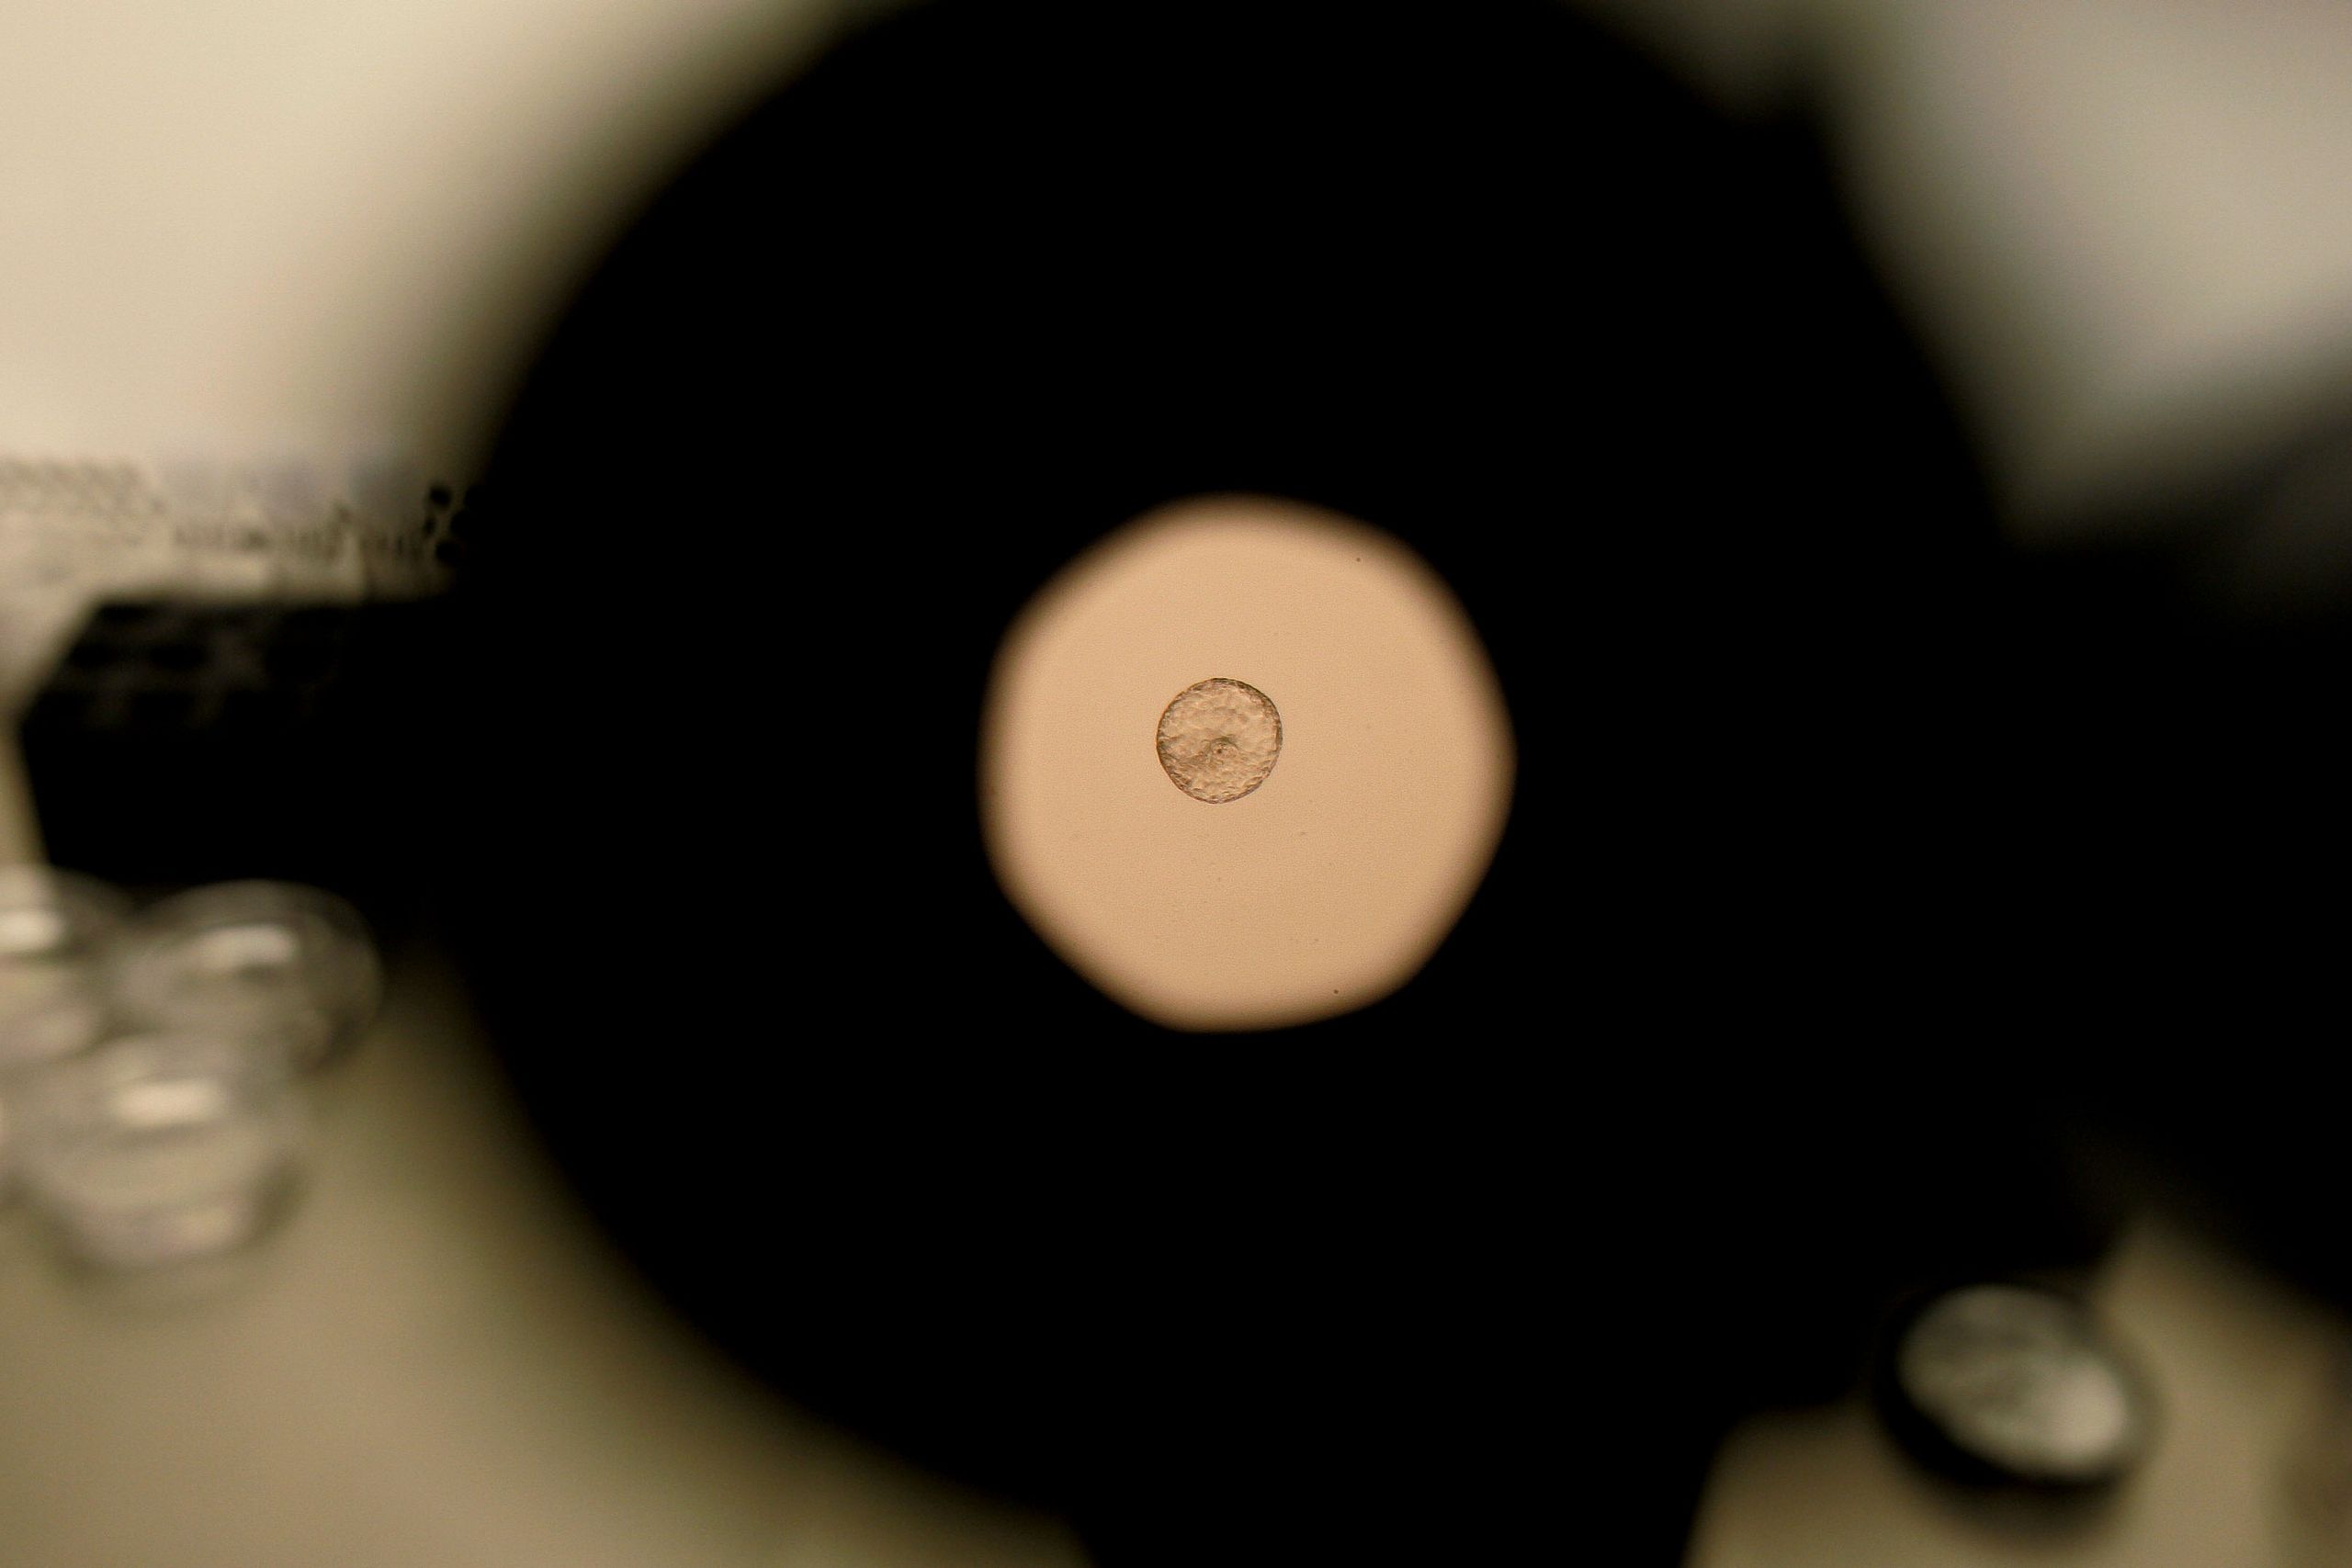

Peneliti dari IBEC mengembangkan simulasi rahim buatan menggunakan gel kolagen, memberikan kesempatan pertama untuk melihat bagaimana embrio manusia secara aktif menembus dan berinteraksi dengan jaringan rahim melalui mikroskop fluoresensi.

Hasil pengamatan menunjukkan embrio manusia bukan hanya menempel di rahim, melainkan menarik dan mengatur ulang matriks rahim dengan kekuatan mekanis, menjelaskan juga mengapa beberapa wanita merasakan nyeri saat implantasi berlangsung.

Perbandingan dengan implantasi pada tikus menunjukkan manusia memiliki cara yang berbeda dan lebih invasif untuk menempel di rahim. Embrio manusia juga merespons rangsangan luar dengan mengubah struktur internalnya, mengindikasikan implantasi adalah proses aktif dan kompleks.